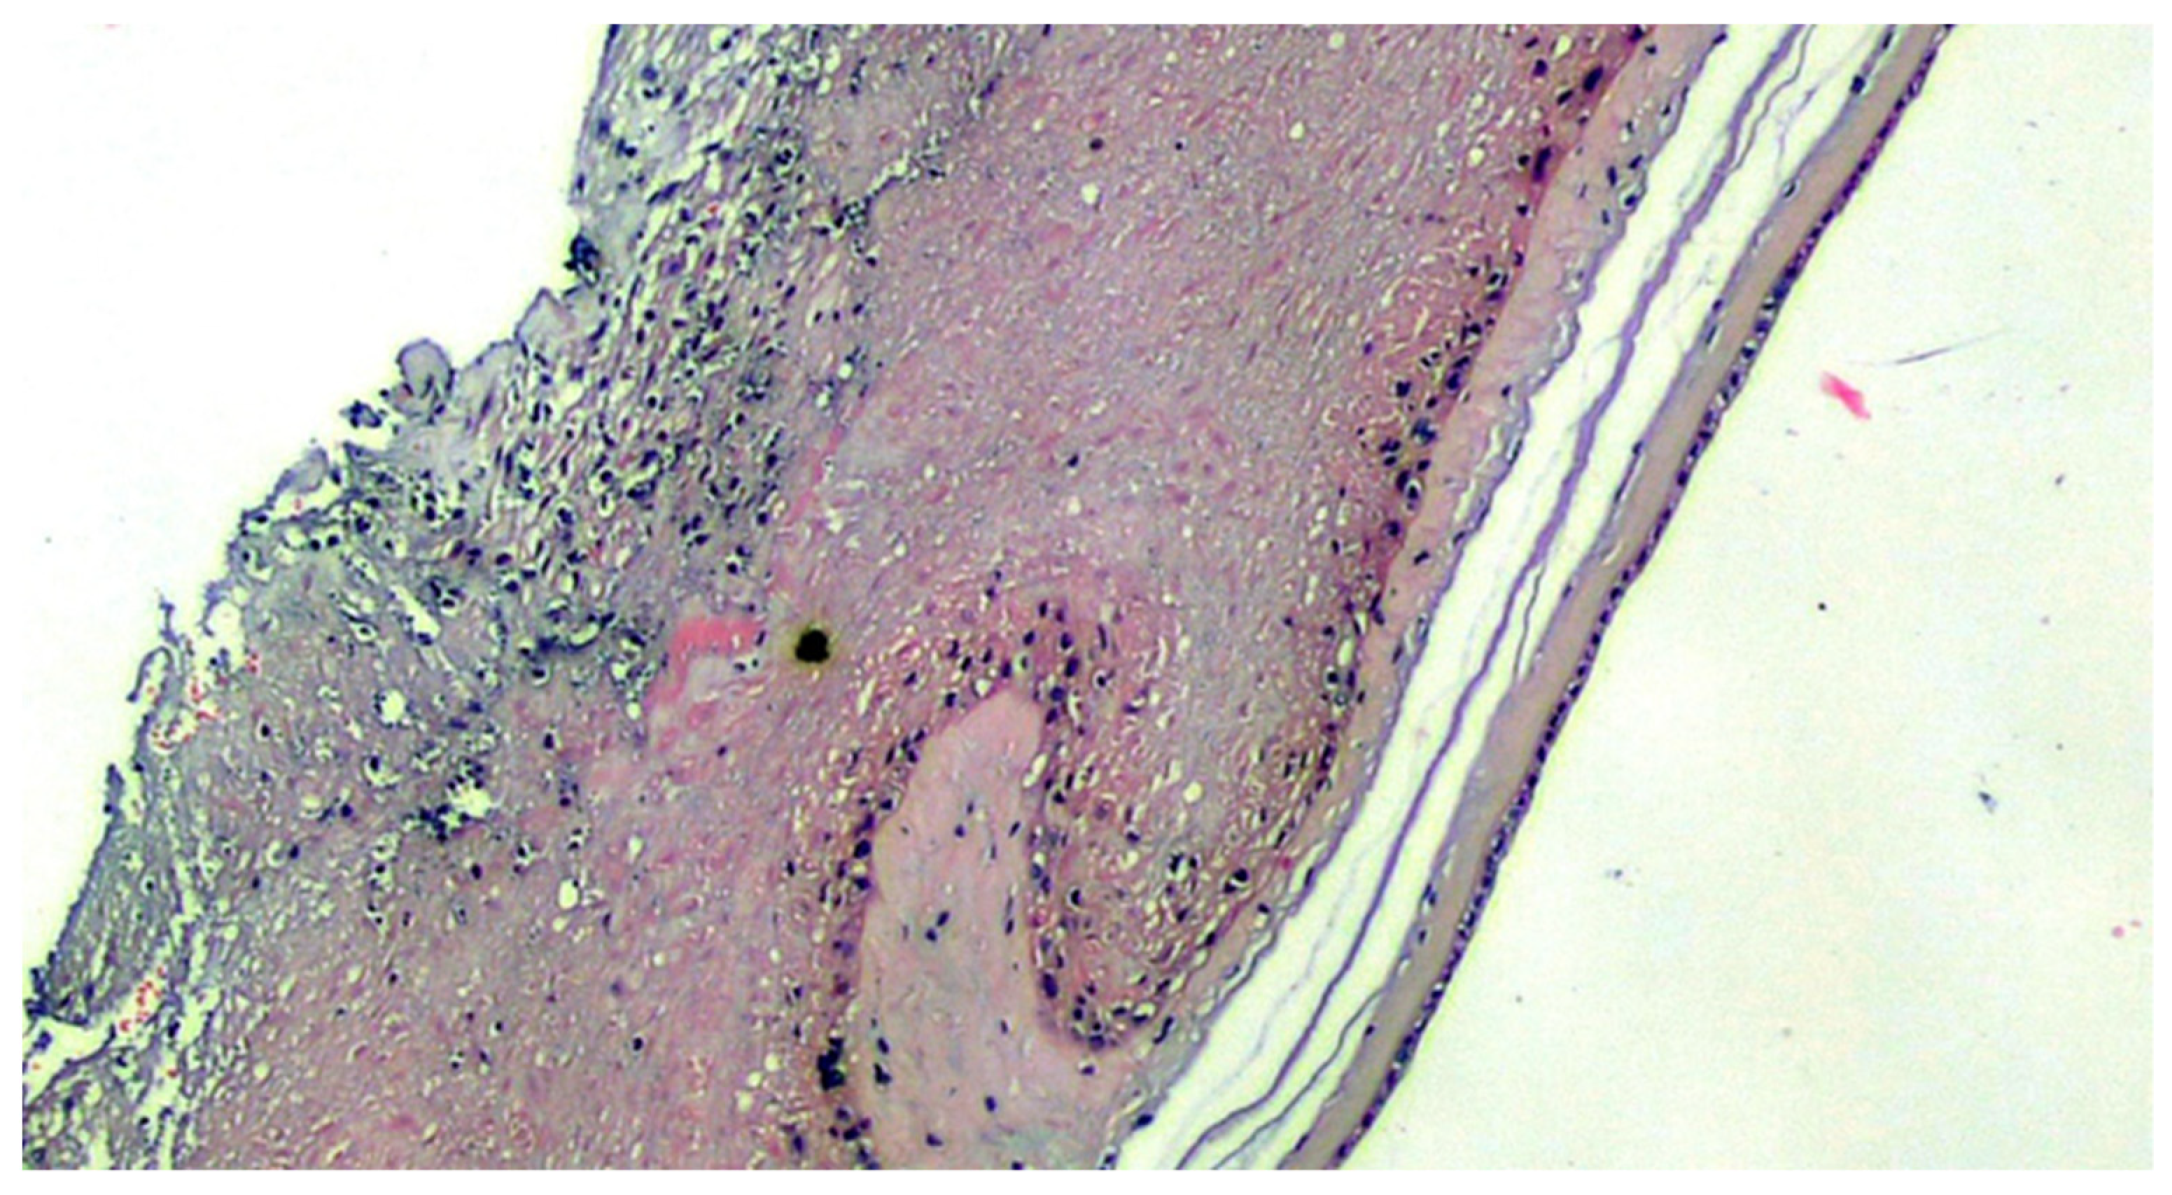

Figure 3.

Basal deciduitis with a little trophoblastic component (superficial implant) and with few inflammatory cells (H&E, 200×).